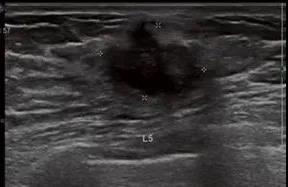

良性叶状肿瘤:女,39,肿块大小4.7㎝,边界清,假包膜,典型裂隙状,血流丰富,表现为典型叶状肿瘤超声表现,但是与交界性难以区分。